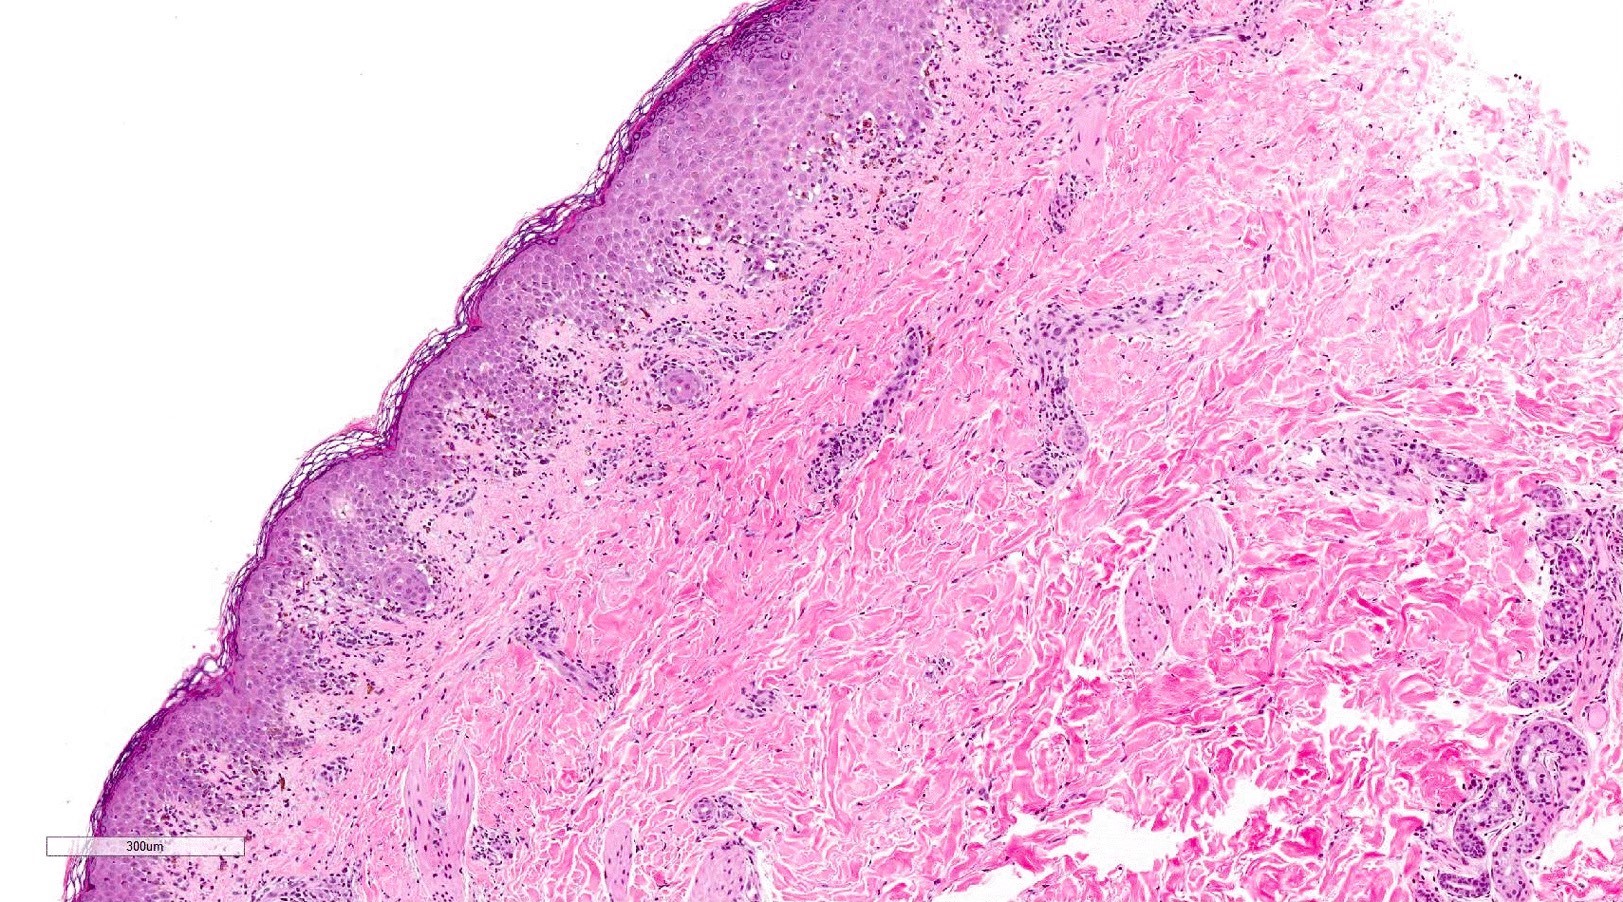

Microscopic (histologic) description

- Acute GVHD (Patterson: Weedon's Skin Pathology, 4th Edition, 2015)

- Mild to moderate superficial perivascular lymphocytic infiltrate with exocytosis of inflammatory cells into the epidermis and basal vacuolation, interface dermatitis

- Scattered, shrunken, eosinophilic keratinocytes with pyknotic nuclei, at all levels of the epidermis; often accompanied by 2 or more lymphocytes, producing the satellite cell necrosis - lymphocyte associated apoptosis

- Occasionally, rare eosinophils can be present; melanin incontinence is prominent in patients with darker skin types

- If severe, subepidermal microvesicles, subepidermal blisters and epidermal necrosis

- Lymphocytic infiltrate in GVHD after solid organ transplantation is usually brisk in comparison to the sparser inflammation following bone marrow transplantation

Microscopic (histologic) images

Contributed by Silvija P. Gottesman, M.D. and Ohoud Aljarbou, M.D.